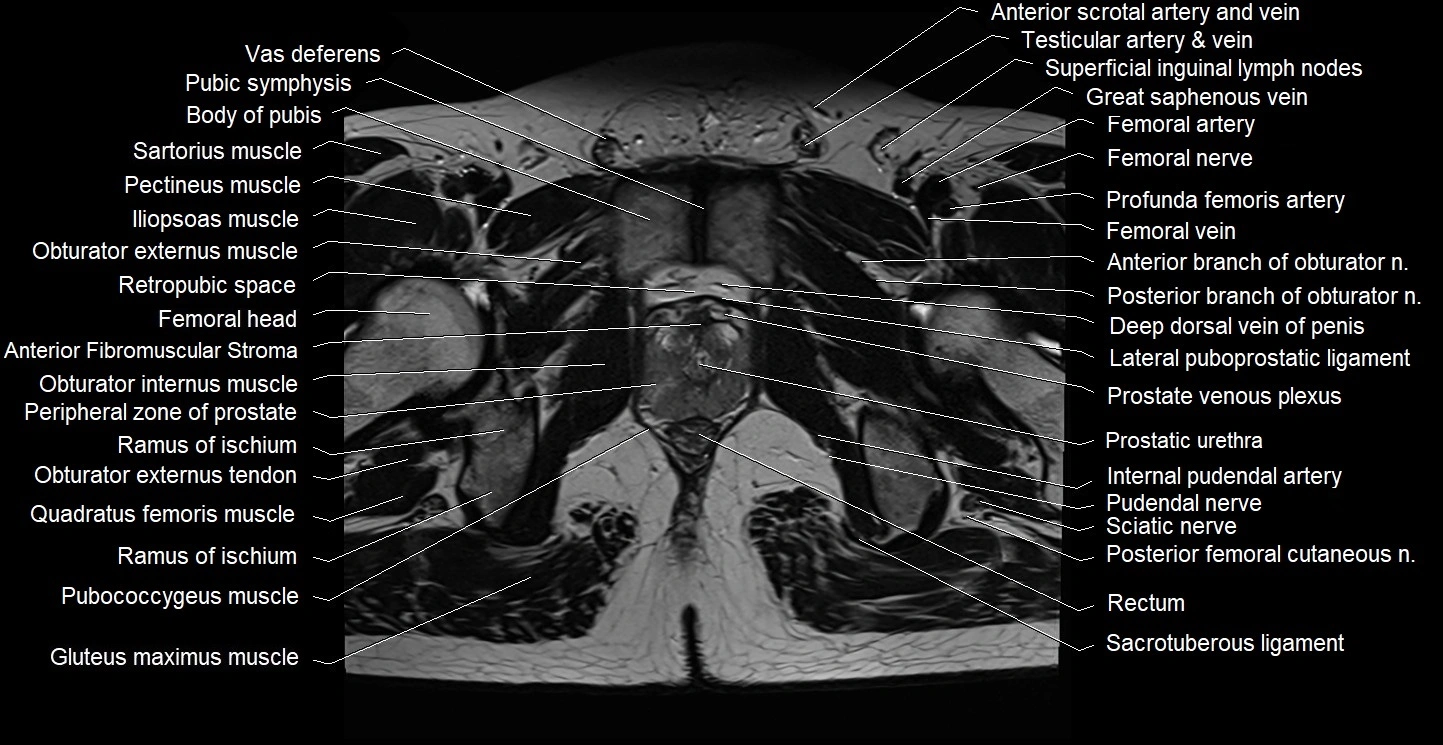

- Acetabulum

- Adductor brevis muscle

- Adductor longus muscle

- Adductor magnus muscle

- Adductor minimus muscle

- Anterior Fibromuscular Stroma of prostate

- Anterior division of obturator nerve (Anterior branch of obturator nerve)

- Body of pubis

- Deep dorsal vein of penis

- Deep femoral artery (profunda femoris)

- Femoral artery

- Femoral nerve

- Femoral vein

- Gluteus maximus muscle

- Head of femur

- Iliopsoas muscle

- Obturator externus muscle

- Obturator externus tendon

- Obturator internus muscle

- Pectineus muscle

- Peripheral zone of prostate

- Posterior femoral cutaneous nerve

- Prostatic urethra

- Pubic symphysis

- Pubococcygeus muscle

- Pudendal nerve

- Quadratus femoris muscle

- Ramus of ischium

- Rectum

- Retropubic space

- Sacrotuberous ligament

- Sartorius muscle

- Sciatic nerve

- Superficial inguinal lymph nodes